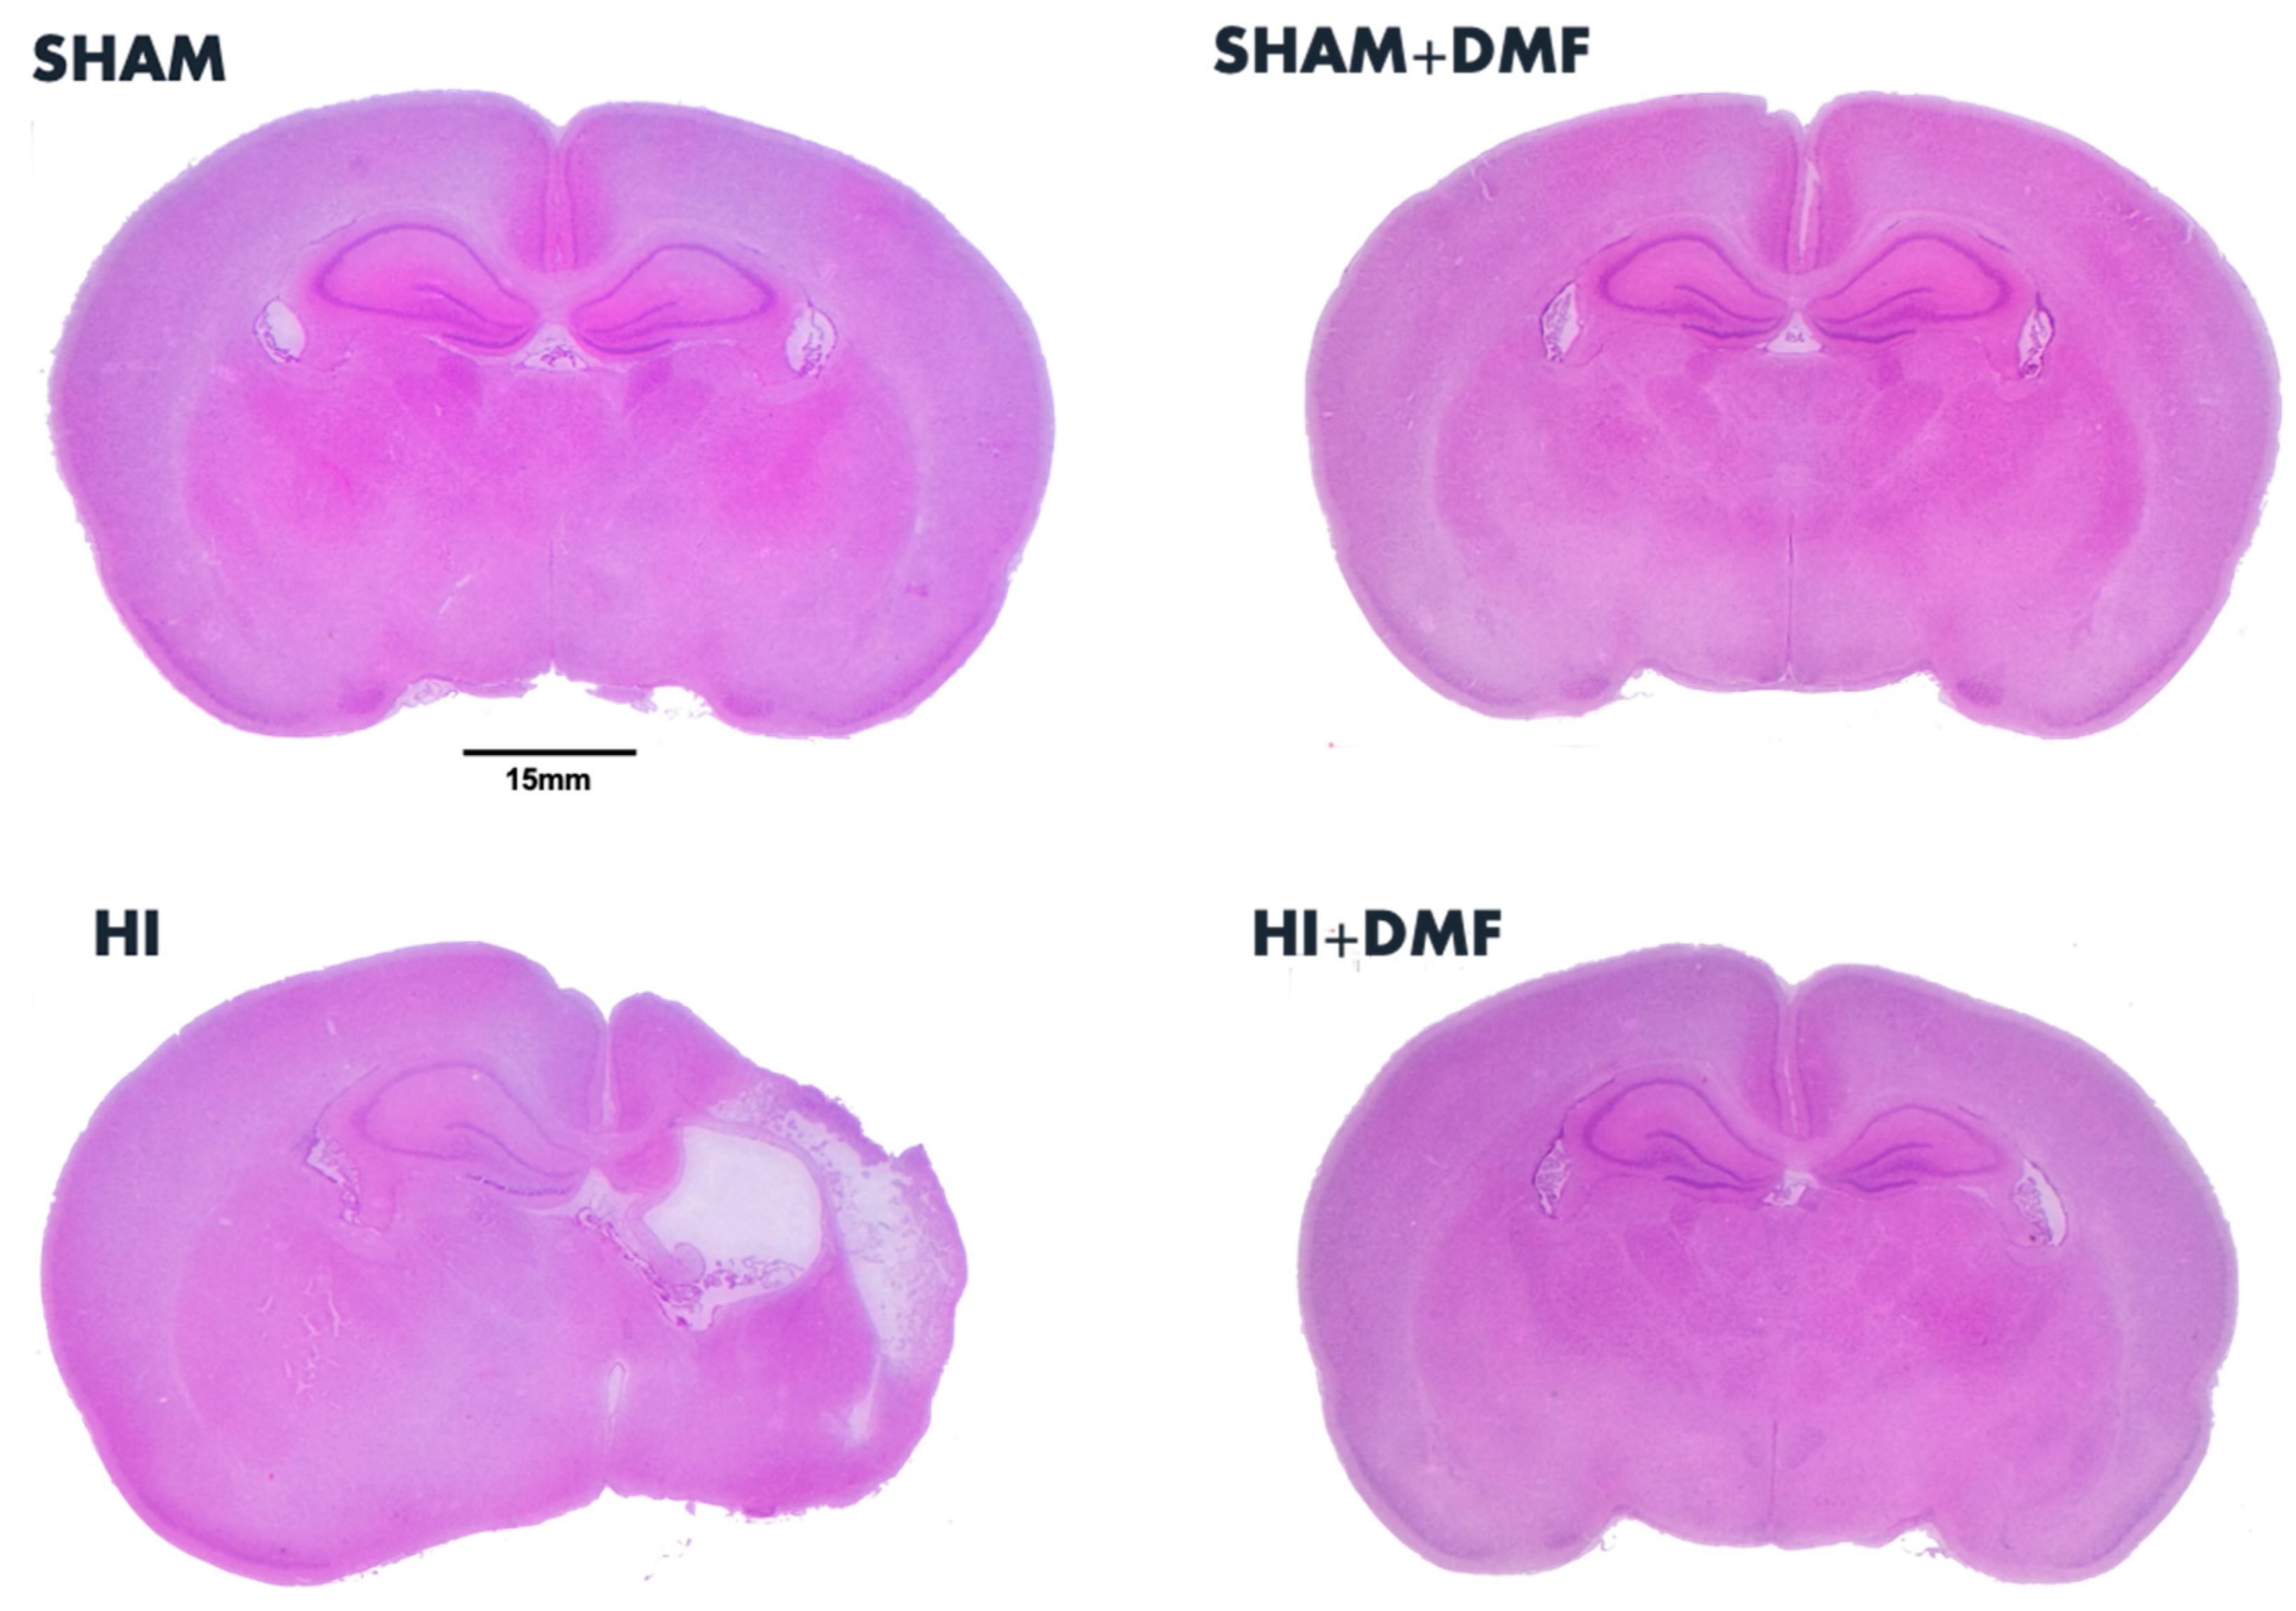

3.2. Brain Area Loss